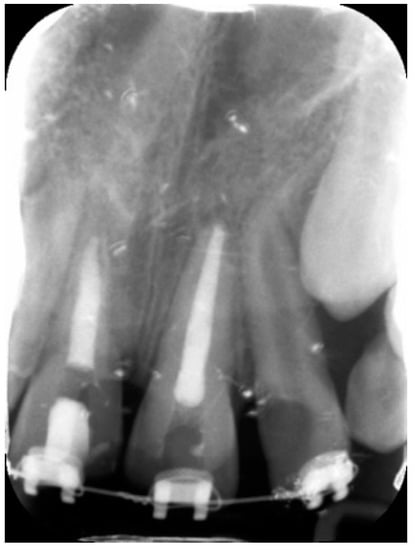

External Root Resorption Management of an Avulsed and Reimplanted Central Incisor: A Case Report

2. Case Report